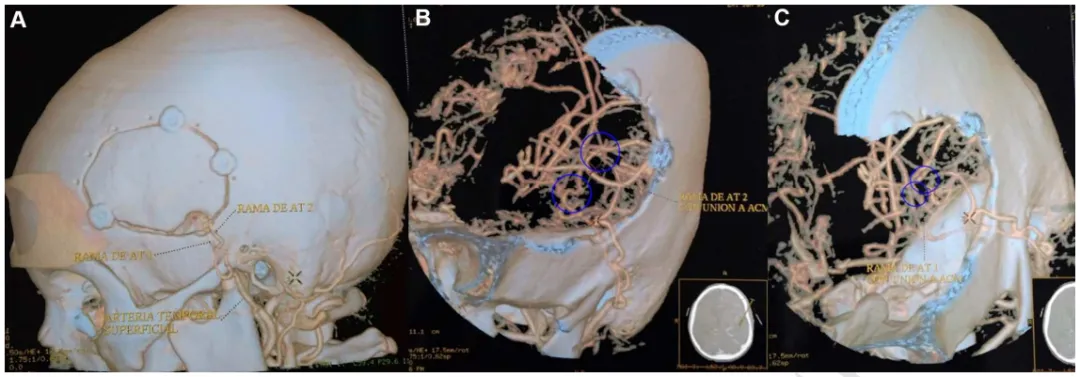

B&C,浩一术前影像

浩一术后CTA的3D重建显示开颅手术大小,以及在左侧颞浅动脉和左侧大脑中动脉之间进行的两次搭桥血管重建。